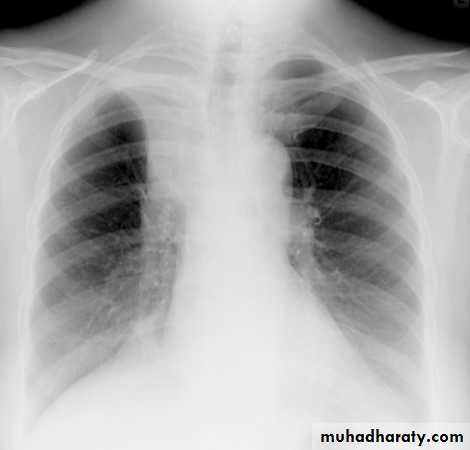

Pulmonary emphysema

Pulmonary emphysema is defined as the "abnormal permanent enlargement of the airspaces distal to the terminal bronchioles accompanied by destruction of the alveolar wall and without obvious fibrosis". Emphysema is one of the entities grouped together as chronic obstructive pulmonary diseaseRadiographic features

Plain film

Except in the case of very advanced disease with bulla formation, chest radiography does not image emphysema directly, but rather infers the diagnosis due to associated features :

hyperinflation:

1.flattened hemidiaphragm(s): most reliable sign

2.ncreased and usually irregular radiolucency of the lungs

3.increased retrosternal airspace

4.increased antero-posterior diameter of chest

5.widely spaced ribs

6.sternal bowing

7.tenting of the diaphragm

8.saber-sheath trachea

9.vascular changes paucity of blood vessels ( absent pulmonary markings in outer 1/3 of the lung fields )

10 .pulmonary arterial hypertension

pruning of peripheral vessels

increased calibre of central arteries

right ventricular enlargement

Emphyzema